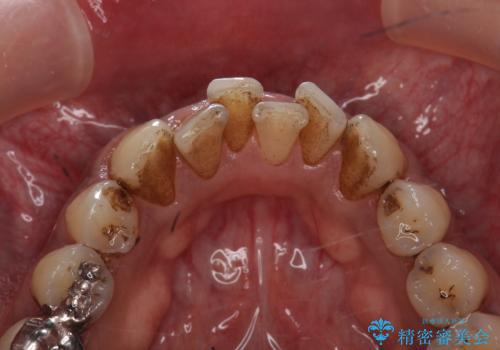

タバコによるヤニ、着色、歯の汚れをPMTC(60分コース)で除去。

- 長年の喫煙による歯の着色をきれいにしたいと、来院されました。

全体にかなり付着していましたので、PMTC(医院で行うプロフェッショナルクリーニング)60分コースを

おすすめしました。

PMTC(60分コース) 担当衛生士 進藤

着色だけでなく歯の表面の汚れもきれいにし、歯の表面がツルツルになって

気持ちがいいと、大変満足していただけました。